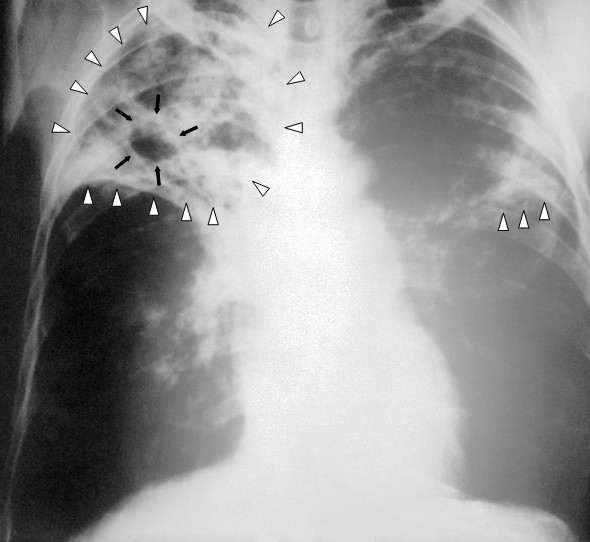

B検査診断

ツベルクリン反応検査

喀痰塗抹検査(チール・ニールセン染色)

胸部X腺検査 など

Wikipedia 肺結核